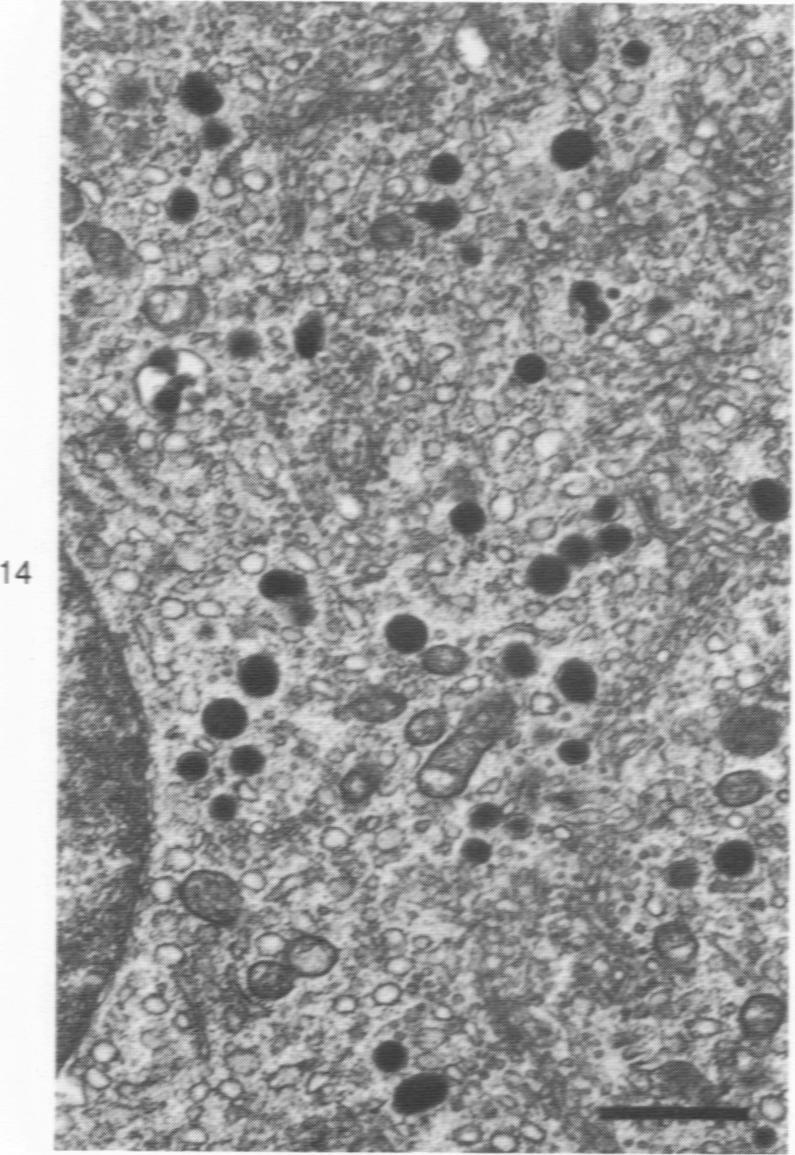

Eighteen cases of medullary carcinoma of the thyroid were analyzed immunohistochemically for calcitonin- and ACTH-containing cells, and tumor cells in 8 cases were examined by an electron microscope and analyzed by manual and computer procedures with particular attention paid to the size and quality of secretory granules. Calcitonin- and ACTH-containing cells were found singly or in clusters in 14 and 11 tumors, respectively. In 4 cases, calcitonin-positive cell clusters and an increase in number of singly scattered C cells were seen apart from the main tumor, suggesting a multicentric nature of certain medullary carcinomas. Some ACTH-containing cells were apparently also positive for calcitonin. In a case of familial Sipple disease, follicular lining cells were replaced in areas with ACTH-containing cells. Three to five frequency distribution curves of the size of secretory granules were obtained in all of 6 cases analyzed, and at least two different types of granule matrix were identified.

对18例甲状腺髓样癌进行免疫组织化学分析,以检测降钙素和促肾上腺皮质激素(ACTH)细胞,并对其中8例肿瘤细胞进行电子显微镜检查,同时采用手工和计算机程序进行分析,特别关注分泌颗粒的大小和质量。分别在14例和11例肿瘤中发现了单个或成簇的降钙素细胞和ACTH细胞。在4例中,除主要肿瘤外,还可见降钙素阳性细胞簇和单个散在C细胞数量增加,提示某些甲状腺髓样癌具有多中心性。一些ACTH细胞显然也对降钙素呈阳性反应。在一例家族性西普尔病中,滤泡衬里细胞部分被ACTH细胞取代。在所有分析的6例中均获得了三到五条分泌颗粒大小的频率分布曲线,并且鉴定出至少两种不同类型的颗粒基质。